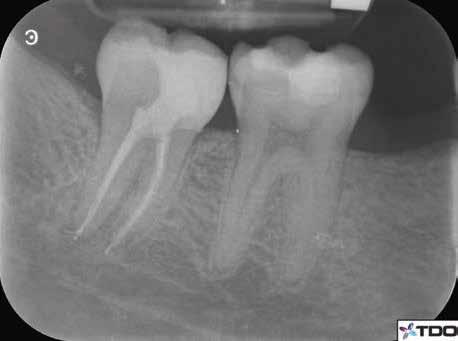

6. a–d. ábrák: A bal alsó második nagyőrlőfogon (3.7) kialakított konzervatív hozzáférési nyíláson keresztül végzett endodonciai kezelés lépései. A mezialis gyökér jelentős mértékben görbült. A gyökértömés hidraulikus kondenzációs technikával készült.

b. ábrák: A jobb alsó első nagyőrlőfogon (4.6) lévő cirkóniumkoronán keresztül elvégzett endodonciai kezelés. A hozzáférési nyílás kialakítása a lehető legkonzervatívabb módon történt. A gyökértömés hidraulikus kondenzációs technikával készült.

egyszerű obturációs technika, az anyag viszkozitási tulajdonságai és a pulpakamra viszonylag egyszerű tisztíthatósága a kezelésünk prognózisának veszélyeztetése nélkül teszi lehetővé az endodonciai beavatkozások lehető legkonzervatívabb módon történő kivitelezését. A bemutatott esetek ellátása során az Aurum Blue rendszert (Meta Biomed) használtuk a gyökércsatornák megmunkálására, míg a gyökértömés elkészítése során hideg hidraulikus kondenzációs technikát alkalmaztunk a kalcium-szilikát alapú CeraSeal (Meta Biomed) sealer felhasználásával (8. ábra).

Esetbemutatás (2., 3.)

Mindkét esetben irreverzibilis pulpitis miatt vált szükségessé a fogak endodonciai kezelése (6. a-d. és 7. a-b. ábrák). Az esetek ellátása során mindvégig minimálinvazív megközelítést alkalmaztunk. A hozzáférési nyílás kialakításától kezdve az endodonciai kezelés befejezését követő csonkfelépítésig, minden beavatkozás ennek megfelelően történt.